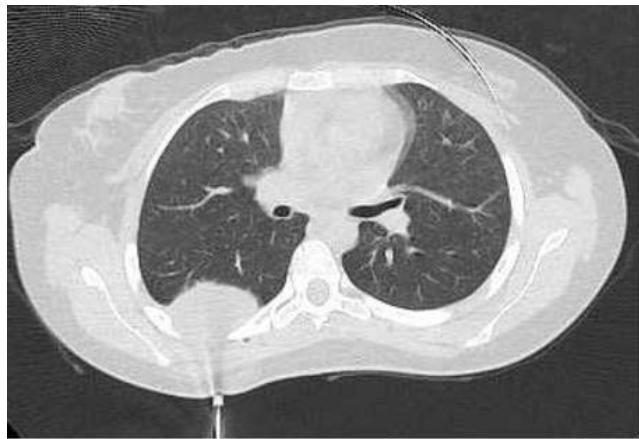

Introduction: Understanding that cancer is a pathology that is challenging to detect, treat, and comprehend is what makes the study of cancer so important. The goal of this case study is to show how a 20-year-old woman was affected by a variety of factors and symptoms that, when combined, raised suspicion of Ewing’s sarcoma, the second most common primary tumor in children and young adults. Ewing’s sarcoma has the characteristics of being an aggressive malignancy originating in the bones.